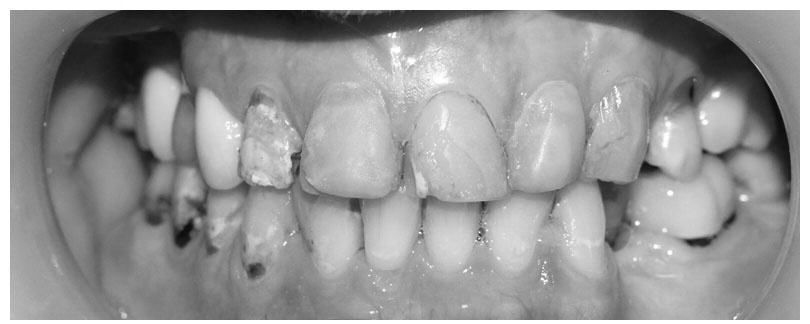

Carley đến từ bang Victoria, Australia. Trước kia cô có hàm răng không được đẹp, bị nhiễm màu nặng, mòn chân răng và sâu răng. Do quá bận rộn với công việc, Carley không có nhiều thời gian điều trị. Cô có ghé qua bệnh viện vài lần để trám răng, có lần làm mão răng sứ. Tuy nhiên, thẩm mỹ không được cải thiện, các mảng trám cũng bắt đầu nhiễm màu.

| Răng trước điều trị. |